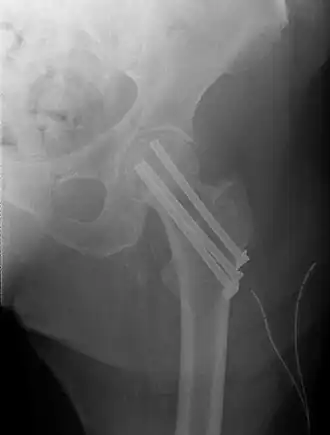

In de meeste gevallen zal er bij een niet-gedislokeerde collumfractuur, gekozen worden voor osteosynthese. Hierbij worden de botdelen aan elkeer gezet door middel van osteosynthesemateriaal zoals de glijdende heupschroef (GHS) of gacannuleerde schroeven.

De gedislokeerde collumfractuur (Garden type 3 en 4) kan zowel worden behandeld door middel van een osteosynthese of door middel van een endoprothese. Deze keuze is afhankelijk van de leeftijd van de patiënt en de lichamelijke en geestelijke conditie. Wanneer er gekozen wordt voor een osteosynthese zal eerst de heupkop weer recht op het dijbeen gezet moeten worden, dit heet repositie. Als deze stand gelijk is aan de normale stand kan er gebruik worden gemaak van osteosynthesemateriaal. Als repositie niet of onvoldoende lukt wordt er alsnog gekozen voor een endoprothese.[1]

De kans dat een pertrochantere fractuur goed geneest, is groot. Behandeling vindt meestal plaats met een dynamische heupschroef: een lange schroef gaat dwars door de fractuur de heupkop in, en wordt op zijn plaats gehouden met een plaatje dat langs het bot van het dijbeen zit geschroefd met enkele schroeven. Meestal is deze botbreuk binnen de 3 tot 6 maanden genezen. Het is, zeker bij ouderen, niet gebruikelijk de dynamische heupschroef weer te verwijderen; de risico’s van een tweede operatie en eventueel van een nieuwe fractuur zijn groter dan de kans op klachten. Wanneer er sprake is van osteoporose kan de kans op een nieuwe fractuur kleiner gemaakt worden door de osteoporose te behandelen. Bij jonge mensen wordt soms wel overwogen de plaat en de schroeven te verwijderen; bij hen kan het materiaal de spanning op het bot vergroten, waardoor de kans op een nieuwe botbreuk bij een ongeluk juist groter wordt.